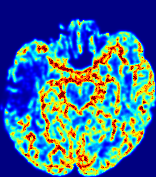

Slice #1Slice #2Slice #3Slice #4Slice #5Slice #6Dgtsuperscript𝐷gtD^{\text{gt}}Refer to captionRefer to captionRefer to captionRefer to captionRefer to captionRefer to captionDestsuperscript𝐷estD^{\text{est}}Refer to captionRefer to captionRefer to captionRefer to captionRefer to captionRefer to captionRefer to caption0.300.300.300.240.240.240.180.180.180.120.120.120.060.060.060.000.000.00(mm2/s)𝑚superscript𝑚2𝑠(mm^{2}/s)𝐕est𝟐subscriptnormsuperscript𝐕est2\|\bf{V}^{\text{est}}\|_{2}Refer to captionRefer to captionRefer to captionRefer to captionRefer to captionRefer to captionRefer to caption0.00300.00300.00300.00240.00240.00240.00180.00180.00180.00120.00120.00120.00060.00060.00060.00000.00000.0000(mm/s)𝑚𝑚𝑠(mm/s)

Figure 15: PIANO identifiability testing: diffusion imaging via advection-diffusion. Top row shows Dgtsuperscript𝐷gtD^{\text{gt}} used for simulating ground truth pure diffusion. Rows below show the estimated Destsuperscript𝐷estD^{\text{est}} and 𝐕est2subscriptnormsuperscript𝐕est2\|{\bf{V}}^{\text{est}}\|_{2} on corresponding slices. Note that the plotted value scale for 𝐕est2subscriptnormsuperscript𝐕est2\|{\bf{V}}^{\text{est}}\|_{2} is 0.01 of that for Dgtsuperscript𝐷gtD^{\text{gt}} and Destsuperscript𝐷estD^{\text{est}}.

Similarly, we test the behavior of PIANO when estimating both advection and diffusion from a pure diffusion-driven process. The goal is to determine if PIANO is able to recognize that there is only diffusion governing the given concentration time-series. We use the same ‘Diffusion Imaging’ data simulation of Sec. 4.2.1 as the concentration dataset, PIANO estimates both velocity 𝐕estsuperscript𝐕est{\bf{V}}^{\text{est}} and diffusivity Destsuperscript𝐷estD^{\text{est}}. Estimation results in Fig. 15 confirm PIANO’s identifiability again: the estimated 𝐕est2subscriptnormsuperscript𝐕est2\|{\bf{V}}^{\text{est}}\|_{2} is almost invisible compared to Destsuperscript𝐷estD^{\text{est}}, even plotted with a 1%percent11\% value range compared to that for Destsuperscript𝐷estD^{\text{est}}. On the other hand, Destsuperscript𝐷estD^{\text{est}} achieves comparable estimation performance as ‘Diffusion Imaging via Diffusion’ in which PIANO predicts Destsuperscript𝐷estD^{\text{est}} alone (shown in Fig. 13).